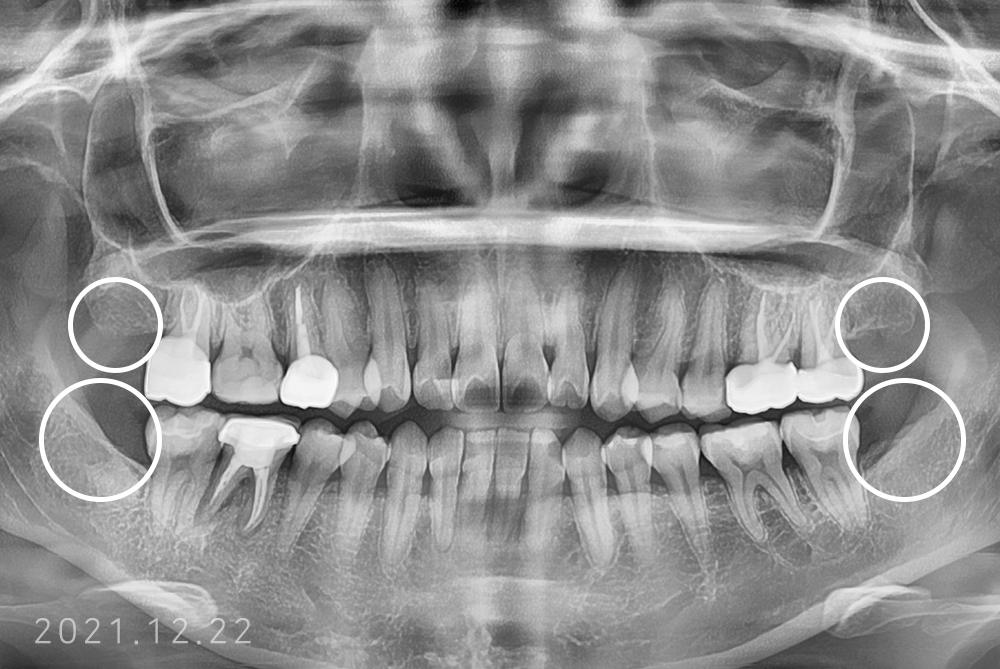

[사랑니] 매복 사랑니 발치

치료전 : 2018-12-20

권은성 후.jpg

치료후 : 2021-12-22

세종치과는 구강악안면외과학 박사이신 원장님이 발치하는 치과입니다.